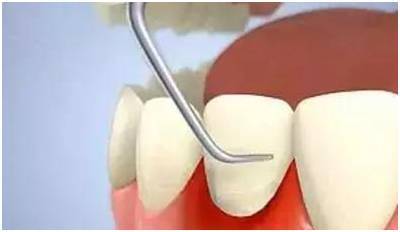

牙周基础治疗相当于大扫除,是把牙齿周围的牙结石等脏东西去掉。它是牙周系统治疗的第一步,适用于每一位牙周患病治疗者,目的在于找到病因,减少牙菌斑,有效控制牙龈炎症,保证下面治疗得以顺利进行。

除了大家熟悉的"洗牙",牙周的基础治疗还有很多内容,如龈下刮治术、拔除无保留作用的患牙等。